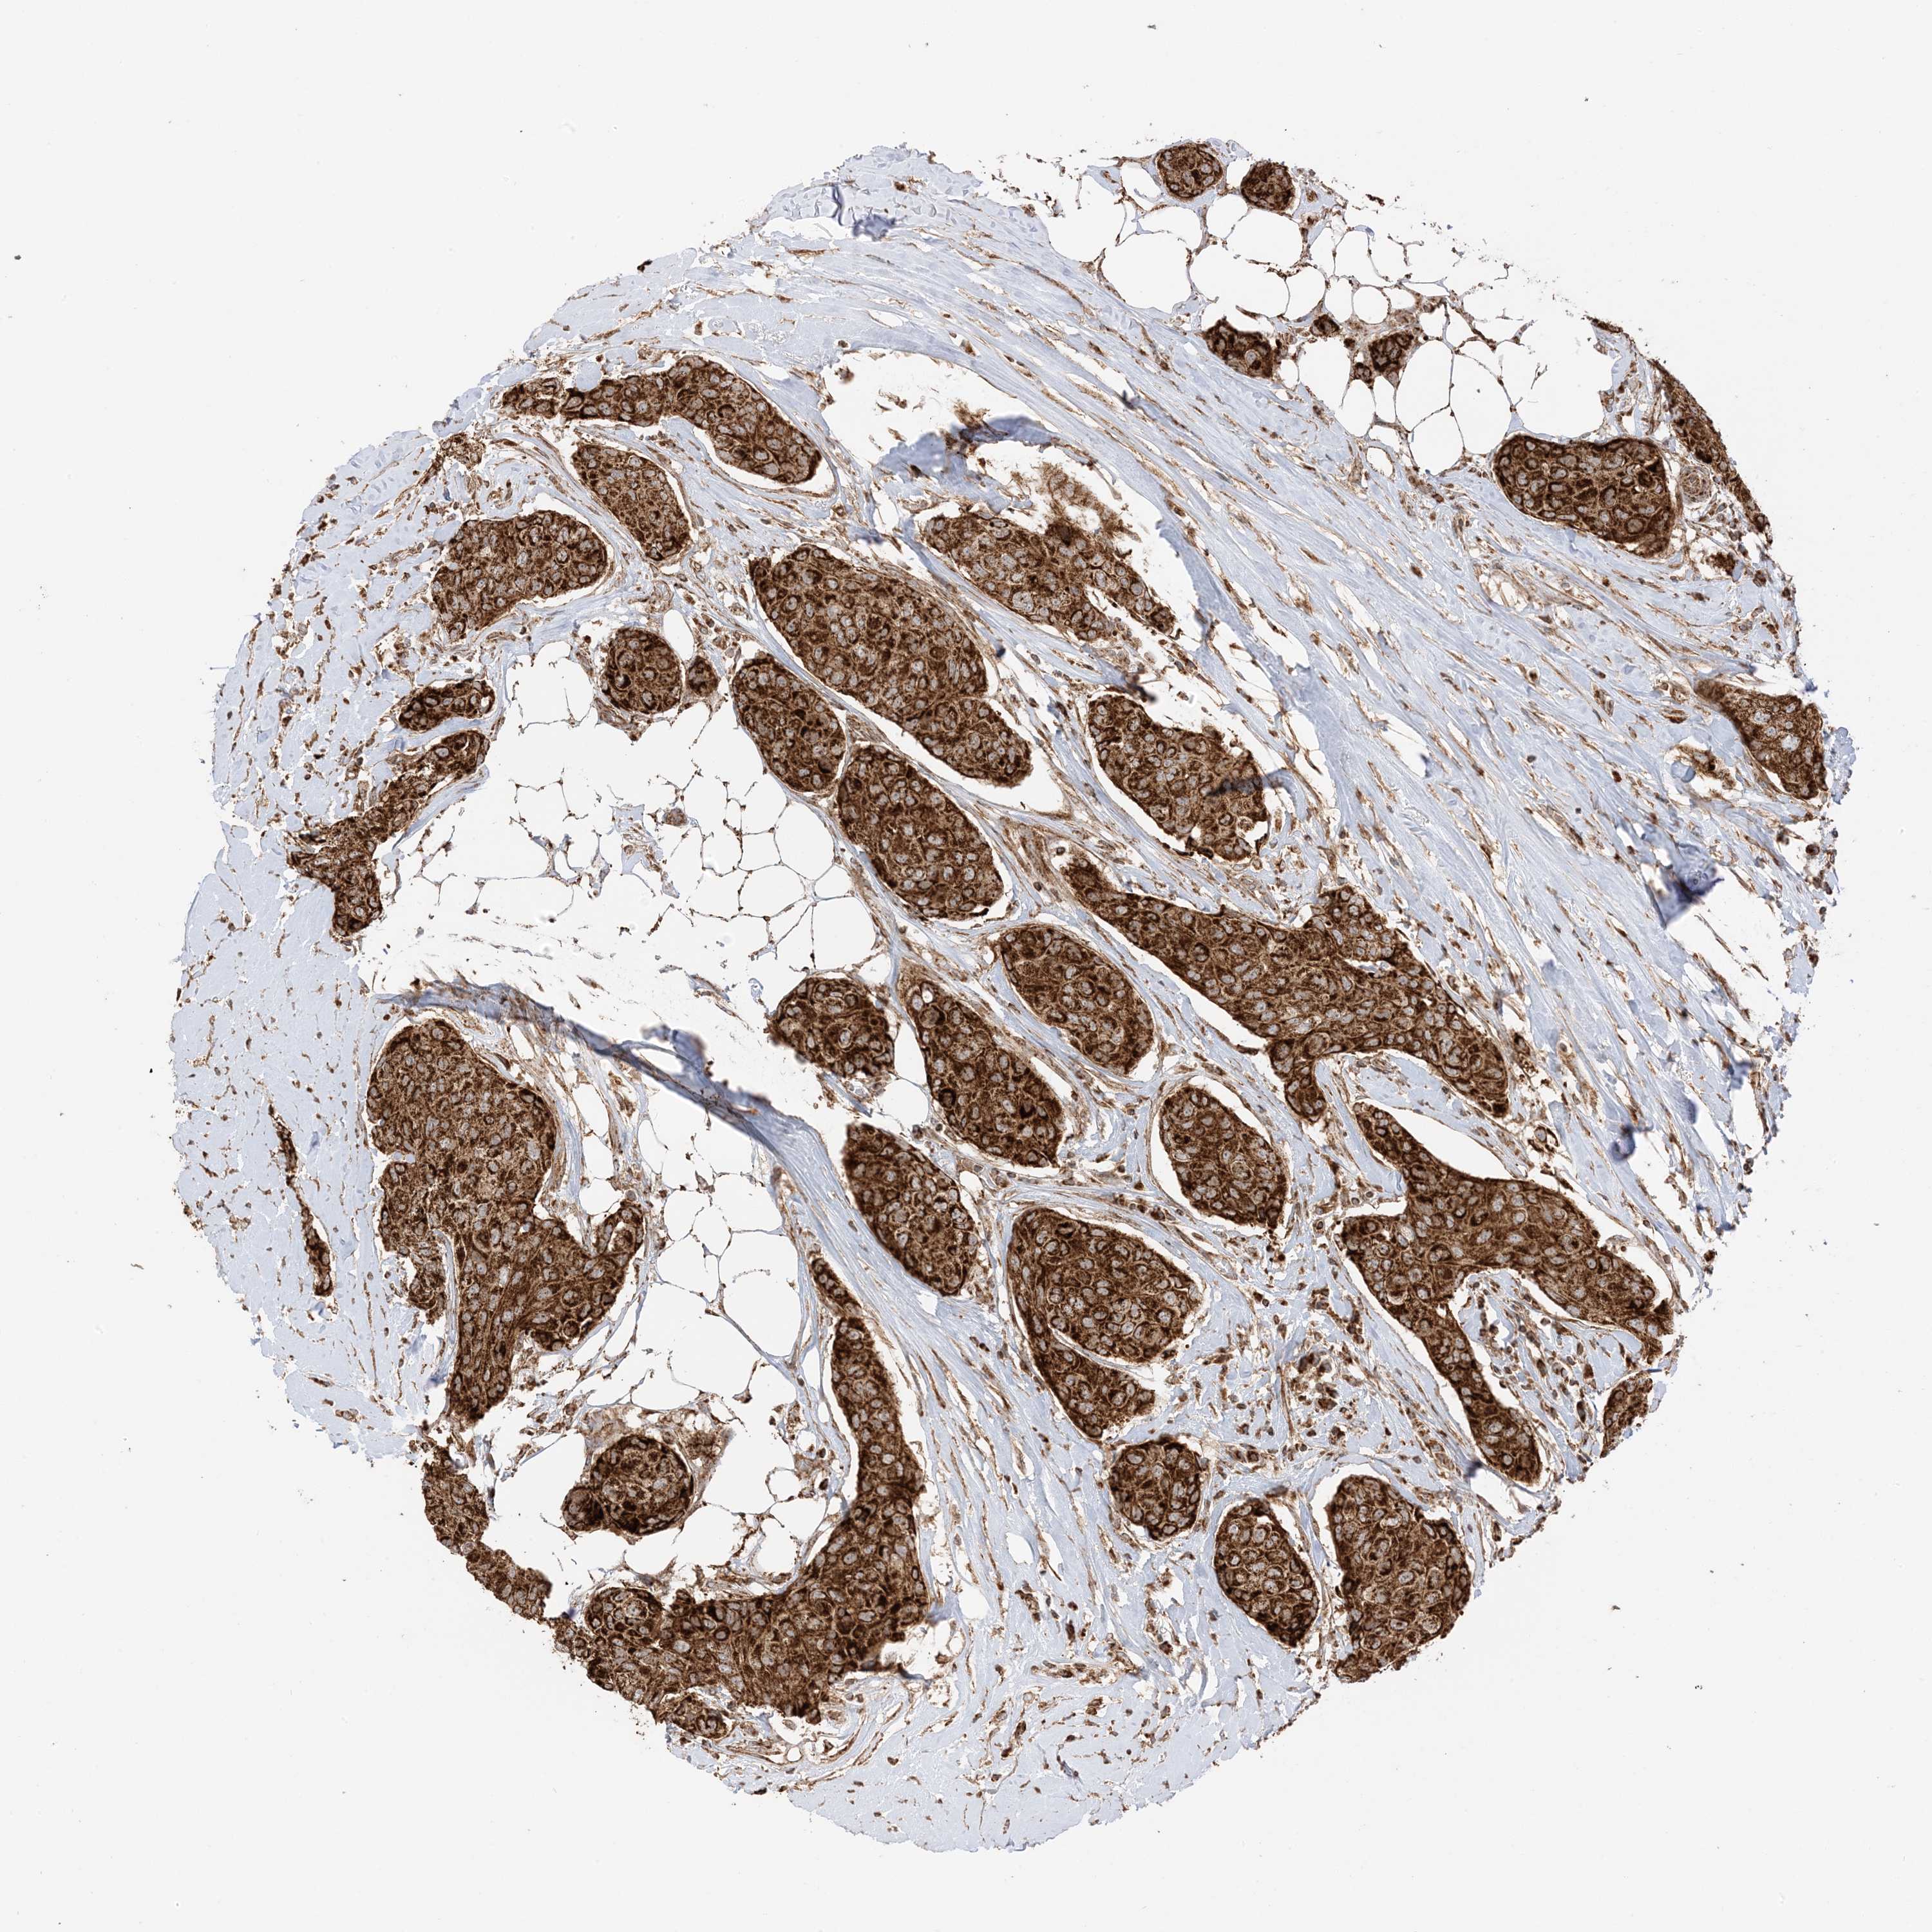

CANCER BREAST CANCER Show tissue menu

BRCA TCGA BRCA VALIDATION PROTEIN EXPRESSION